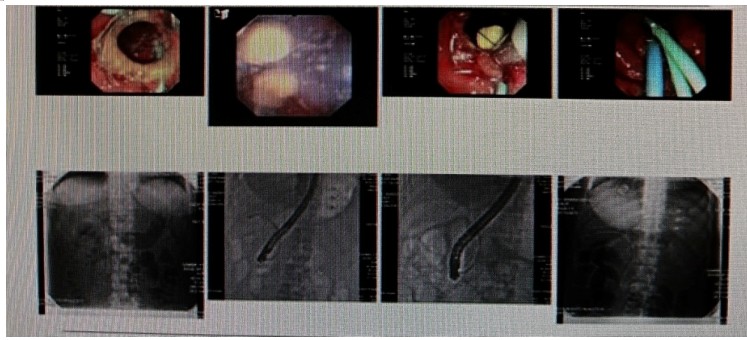

消化內(nèi)科肝病亞??茍F(tuán)隊(duì)詳細(xì)討論,分析患者情況后,取消了周女士的肝穿刺活檢檢查,建議患者先行超聲胃鏡下膽胰掃查。在內(nèi)鏡醫(yī)師第三只眼——超聲胃鏡的掃查下,發(fā)現(xiàn)引起周女士肝功能受損的罪魁禍?zhǔn)?/span>原來是膽總管末端結(jié)石!伍友興主任醫(yī)師帶領(lǐng)團(tuán)隊(duì)給予患者行ERCP下取石后,周女士未再出現(xiàn)腹痛,肝功能恢復(fù)正常。

無獨(dú)有偶,劉先生也為反復(fù)出現(xiàn)肝功能受損到多家醫(yī)院就診檢查,未能找到原因,來到衡陽市中心醫(yī)院消化內(nèi)科就診,希望能在肝穿刺活檢下得出病因。在行肝穿刺活檢之前,醫(yī)生建議劉先生行超聲胃鏡膽胰掃查,發(fā)現(xiàn)引起劉先生反復(fù)肝功能受損原因,亦是膽總管結(jié)石引起,在ERCP術(shù)取石術(shù)后,患者肝功能恢復(fù)正常,未再出現(xiàn)異常情況。

張丹霞主任醫(yī)師介紹,超聲內(nèi)鏡通過胃十二指腸自然腔道,可以將探頭貼近相應(yīng)的位置,近距離的觀察胰腺及膽道系統(tǒng),準(zhǔn)確捕捉到直徑小于5毫米的胰腺異常病灶及膽道系統(tǒng)病灶。而體表B超常受皮膚、脂肪或腸道氣體干擾。CT或磁共振檢查只能提供靜態(tài)圖像,且對(duì)膽胰管陰性結(jié)石或是未引起明顯膽管梗阻性的結(jié)石檢查有局限性,因此對(duì)于有輕微腹痛合并肝功能受損的患者,建議常規(guī)行超聲胃鏡下膽胰掃查。超聲胃鏡、腹部彩超、腹部CT、腹部MRI同為診斷膽管細(xì)微病變的四架馬車,在膽總管結(jié)石診斷方面,超聲胃鏡膽胰掃查同ERCP一樣,是敏感性高、特異性強(qiáng)的診斷方法。超聲胃鏡發(fā)現(xiàn)可疑病變,可以完成穿刺活檢,還可行囊腫穿刺引流、膽管減壓、消融術(shù)等。